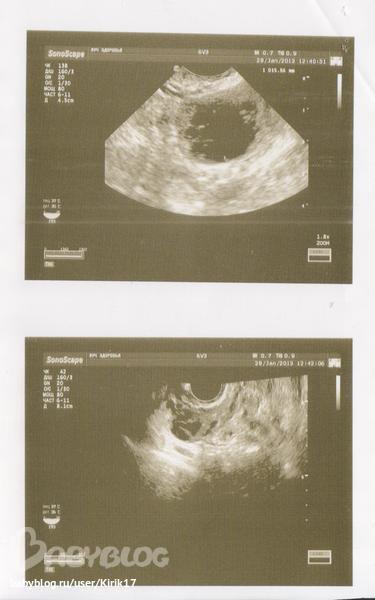

Начала беспокоиться по поводу низкой температуря для 2 фазы. Сейчас сбегала на узи в ближайший медцентр. В итоге мне ничего путного не сказали. Сказали, что фолликул 15мм, что эндометрий соответствует 2ой фазе (9мм секреторный), но про ЖТ и про жидкость вообще ничего ((( Типа этот фолликул и есть ЖТ.. К своему узисту только в субботу..

Раньше, когда он был 24мм, он был ровненький круглый, а сейчас какой-то косой, говорит, что фолликул разорвался.. почему же тогда жидкости нет? Или ее уже к 17 ДЦ не должно быть.. ничего не понимаю. Спросила ее, когда придти, чтобы посмотреть на ЖТ, она сказала, дак вот типа оно, ЖТ.. Голова кругом..

Ага, давай)) Прочитала ее закорючки в ЛЯ фолликул 15мм с неоднородным внутренним содержанием..

Ой, у меня вроде что-то похожее, только более округлое, как обрывками какимито внутри.. может действительно ЖТ? Смутило то, что нет жидкости, прочитала, что регрессия фолликула сопровождается отсутсвием жидкости. Если бы фоолик сдулся, он наверно был бы меньше, но более или менее ровненький.. правильно ведь..?

ЖТ отличается от фолликула как раз внешним видом так сказать. как раз "косой- кривой"

фоликул имеет четкие контуры, черное такое пятно

а ЖТ сероватое и контуры как с рябью

я думаю, что это ЖТ

да, фотку сделали, контуры размытые, с рябью, но оно темноватое..

конечно это не ДФ, а ЖТ!